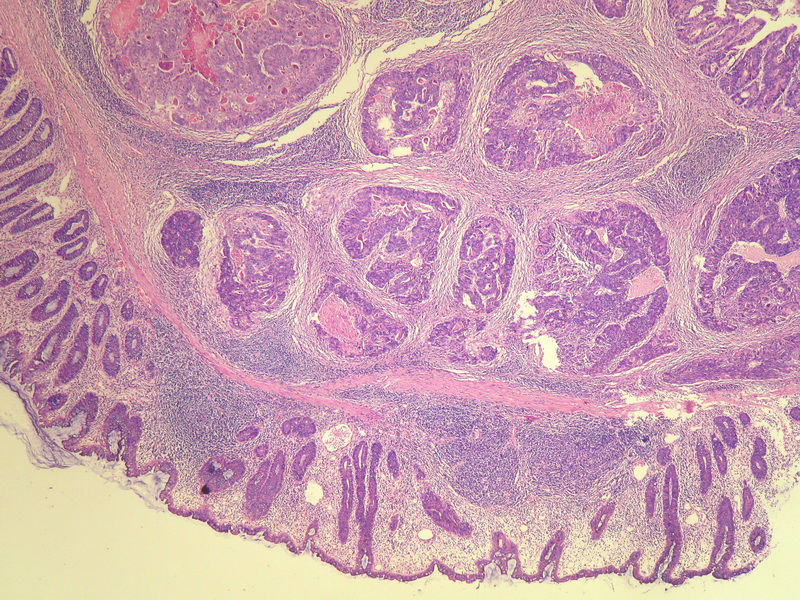

70岁男性,乙状结肠息肉样肿物。

请教:这个乙状结肠肿瘤侵犯到哪一层??图1

×参考诊断

粘膜下层

仅就浸润的深度而言,粘膜下层应该没什么争议。但是肿瘤表面的粘膜腺体是很好的,从低倍图看,不能排除是个转移灶的可能。请临床再查一查除了这个以外别的部位还有没有肿块。

浸润深度为粘膜下层,可粘膜表面的腺体完整,同意楼上的观点。谢谢